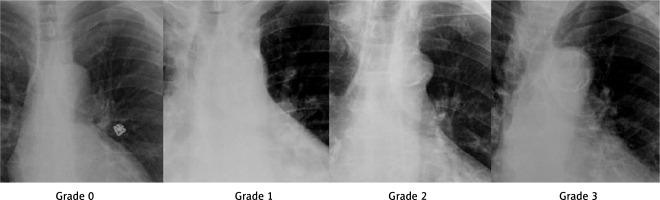

The demographic and laboratory data of the patients included in the study, as presented in Table I, were compared, and no significant differences were found between the PPM and control groups. Table II shows the comparison of the echocardiography, electrocardiography, chest X-ray, and CT data between the groups. The distribution of AKC among the patients in both groups was also examined (Figure 2).

Figure 2

Distribution of aortic knob calcification in groups with and without a permanent pacemaker (PPM) requirement after transaortic valve implantation

The rates of MS (p = 0.013) and AKC (p = 0.002) statistically significantly differed between the PPM and control groups. Table III presents the comparison of the procedural characteristics of the patients, the values obtained after the TAVI procedure, and the mortality results evaluated over an average period of 18 ±4 months. There were no significant differences between the two groups in terms of these parameters.